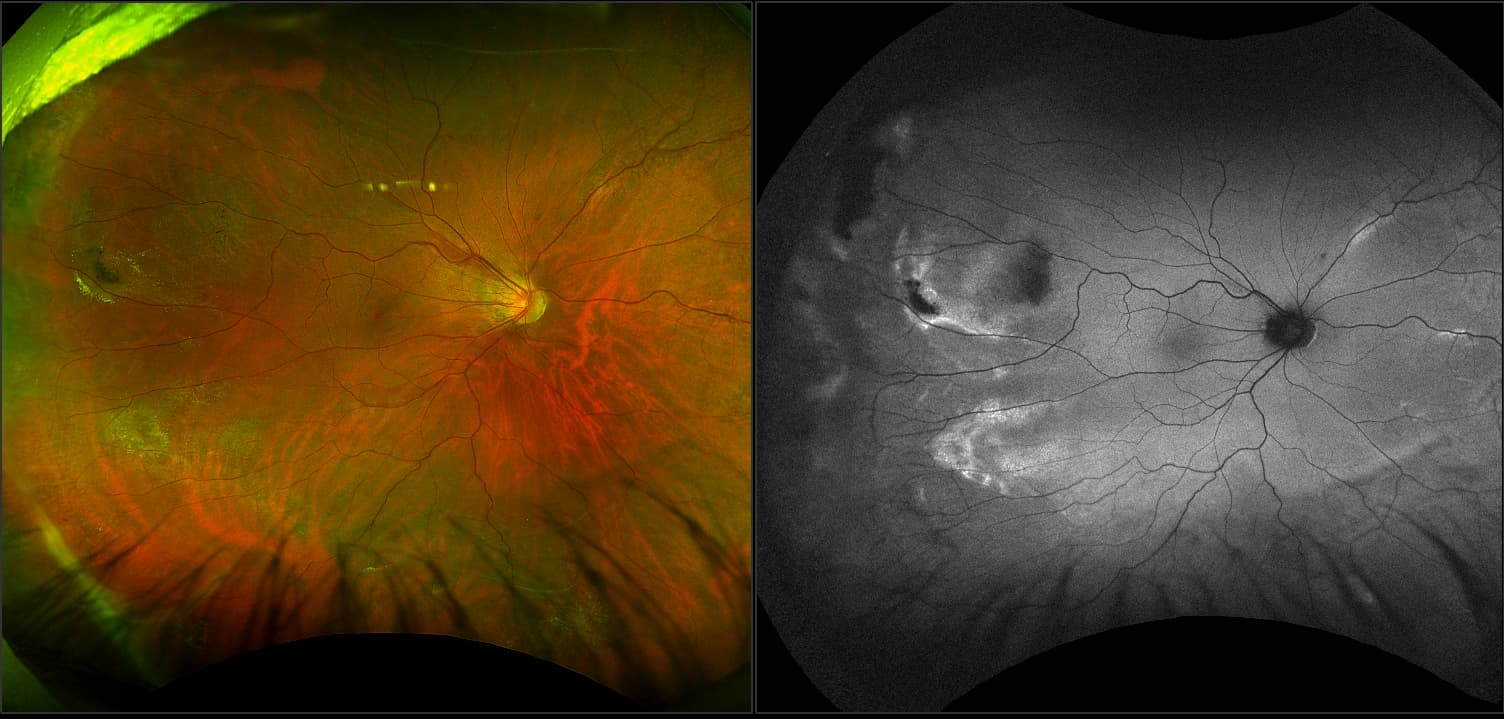

Schisis